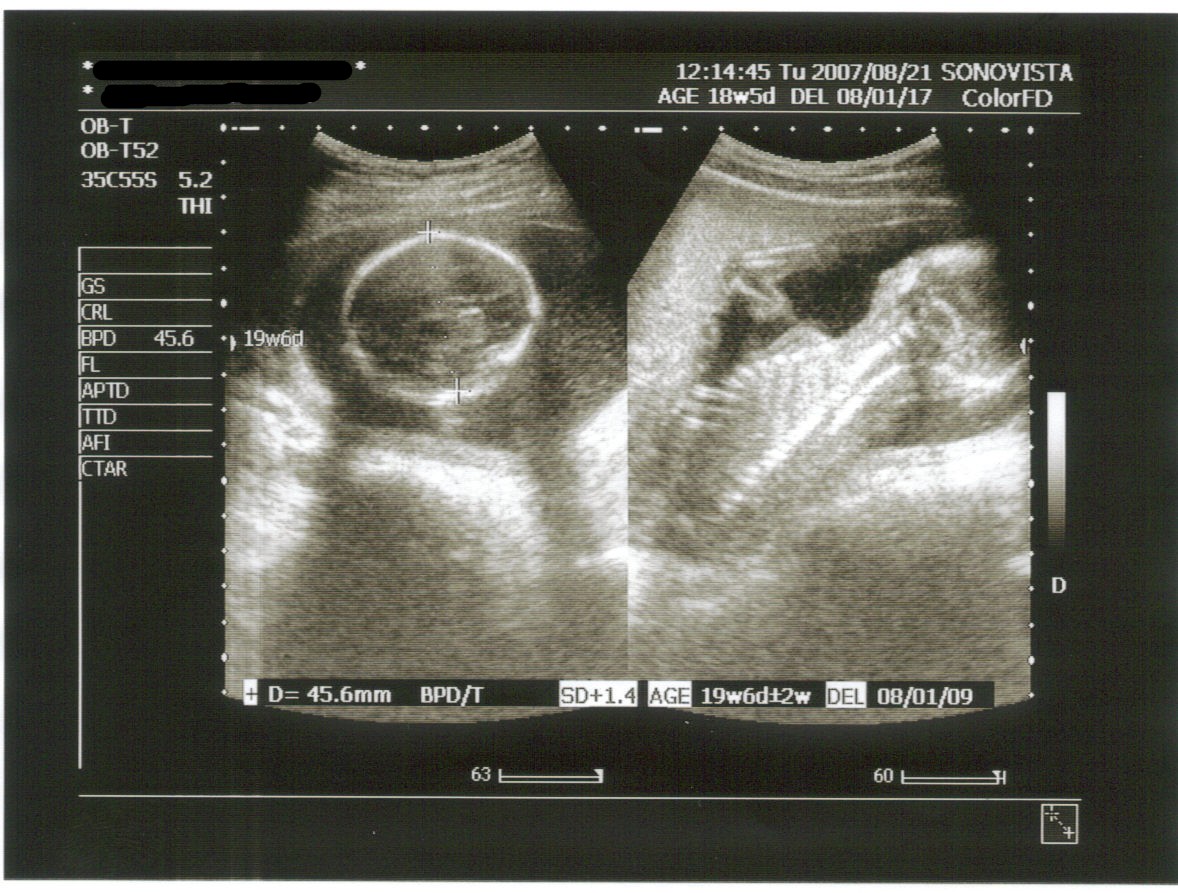

今日はお腹のエコーから。

今日のお腹の中の様子は・・・

今日は逆子状態でした(-_-;)

左が頭で45.6㎜

右は背中側で背骨と肋骨が見えました。

指も5本ハッキリ見えましたよ。

推定体重は281g

狭い所にいるらしく脚のほうがなかなか見えなくて先生困ってました(^_^;)

体重って頭と胴の輪切りと太腿の骨の長さで算出されるんだってさ。

今日のエコーだと週相当20w4d。

現在の週数より少し大きめらしいけど、今はまだ細かく分からないんだって。

もう少し進むといろんなことが分かるらしい。

胎盤の位置も正常で、至って順調だってさ v(^-^)v

「胎動はどうですか?」と聞かれ「何となく・・・確信が持てないんですが・・・」と答えると、「逆子の状態だと感じにくいんですよ。」とのこと。

頭が上だと足が狭い所に入って動きが制限されちゃうみたいね。